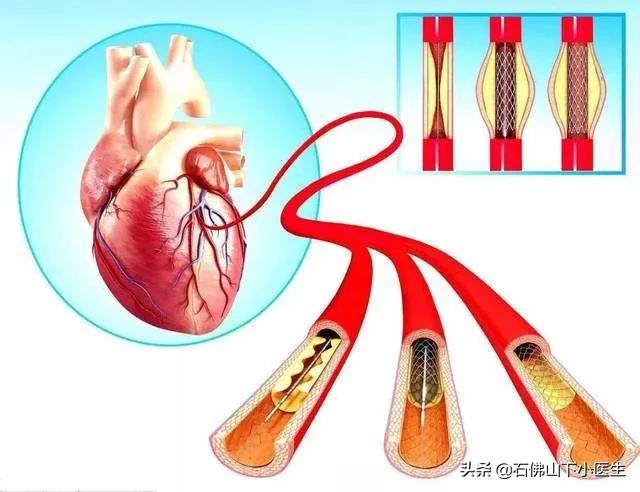

私たちは皆、多かれ少なかれ知っているはずだ。冠状動脈性心臓病とは、主に心臓の冠状動脈が狭くなる病気である。心臓に血液を供給する血管の狭窄は、心筋虚血や心筋壊死を引き起こす可能性があり、この狭窄を解消して冠動脈への血液供給を回復させるために、治療法のひとつは次のようなものである。何か支えとなるものを持っていく。それこそが、今、私たちが話しているブラケットなのだ。

ステップ1、パンク。末梢動脈を見つけ、この動脈から穿刺を行うが、最も一般的な選択は、手の付け根か太ももの末梢動脈を選択することである。

ステップ2、チューブの挿入。その末梢血管開口部からシースを挿入し、適切なサイズのシースを選択してガイドワイヤーを進め、冠動脈開口部付近の心臓までゆっくりと送り込む。

ステップ3:軌道を確立する。最初のガイドワイヤーは冠動脈より太いので、この時は細いガイドワイヤーを選んで冠動脈病変の遠位部を通過させ、まずバルーンで拡張しなければならない。

ステップ4:ステントを留置する。バルーンの拡張が完了したら、このガイドワイヤーに従ってステントを留置する。

治療に介入するためにインターベンショナル・ステント留置術を必要とする心臓疾患は、通常、冠動脈硬化性心血管系疾患(一般に冠動脈性心疾患として知られている)と密接に関連している。

冠状動脈は心臓に血液を供給する主な動脈で、年齢、三高、慢性病、悪習慣などの影響を受けて、心臓に血液を供給する冠状動脈も他の動脈と同じように、アテローム性動脈硬化症、狭窄、プラークなどの問題が現れる、冠状動脈の狭窄が50%以上の場合、通常、心臓の血液供給と酸素供給が大きな影響を受けると考えられ、このような場合、冠状動脈性心臓病と診断することができます。このような場合、冠動脈性心疾患と診断することができる。

心臓ステント留置術は、閉塞した血管にステントを挿入し、閉塞を解除することで心筋への正常な血液と酸素の供給を回復させ、心臓の正常な機能を維持するインターベンショナル手技である。ステント留置術は心臓内で行われ、異物が挿入されるため、多くの患者さんがステント留置術の安全性を心配している。実際、過度の心配は不要である。